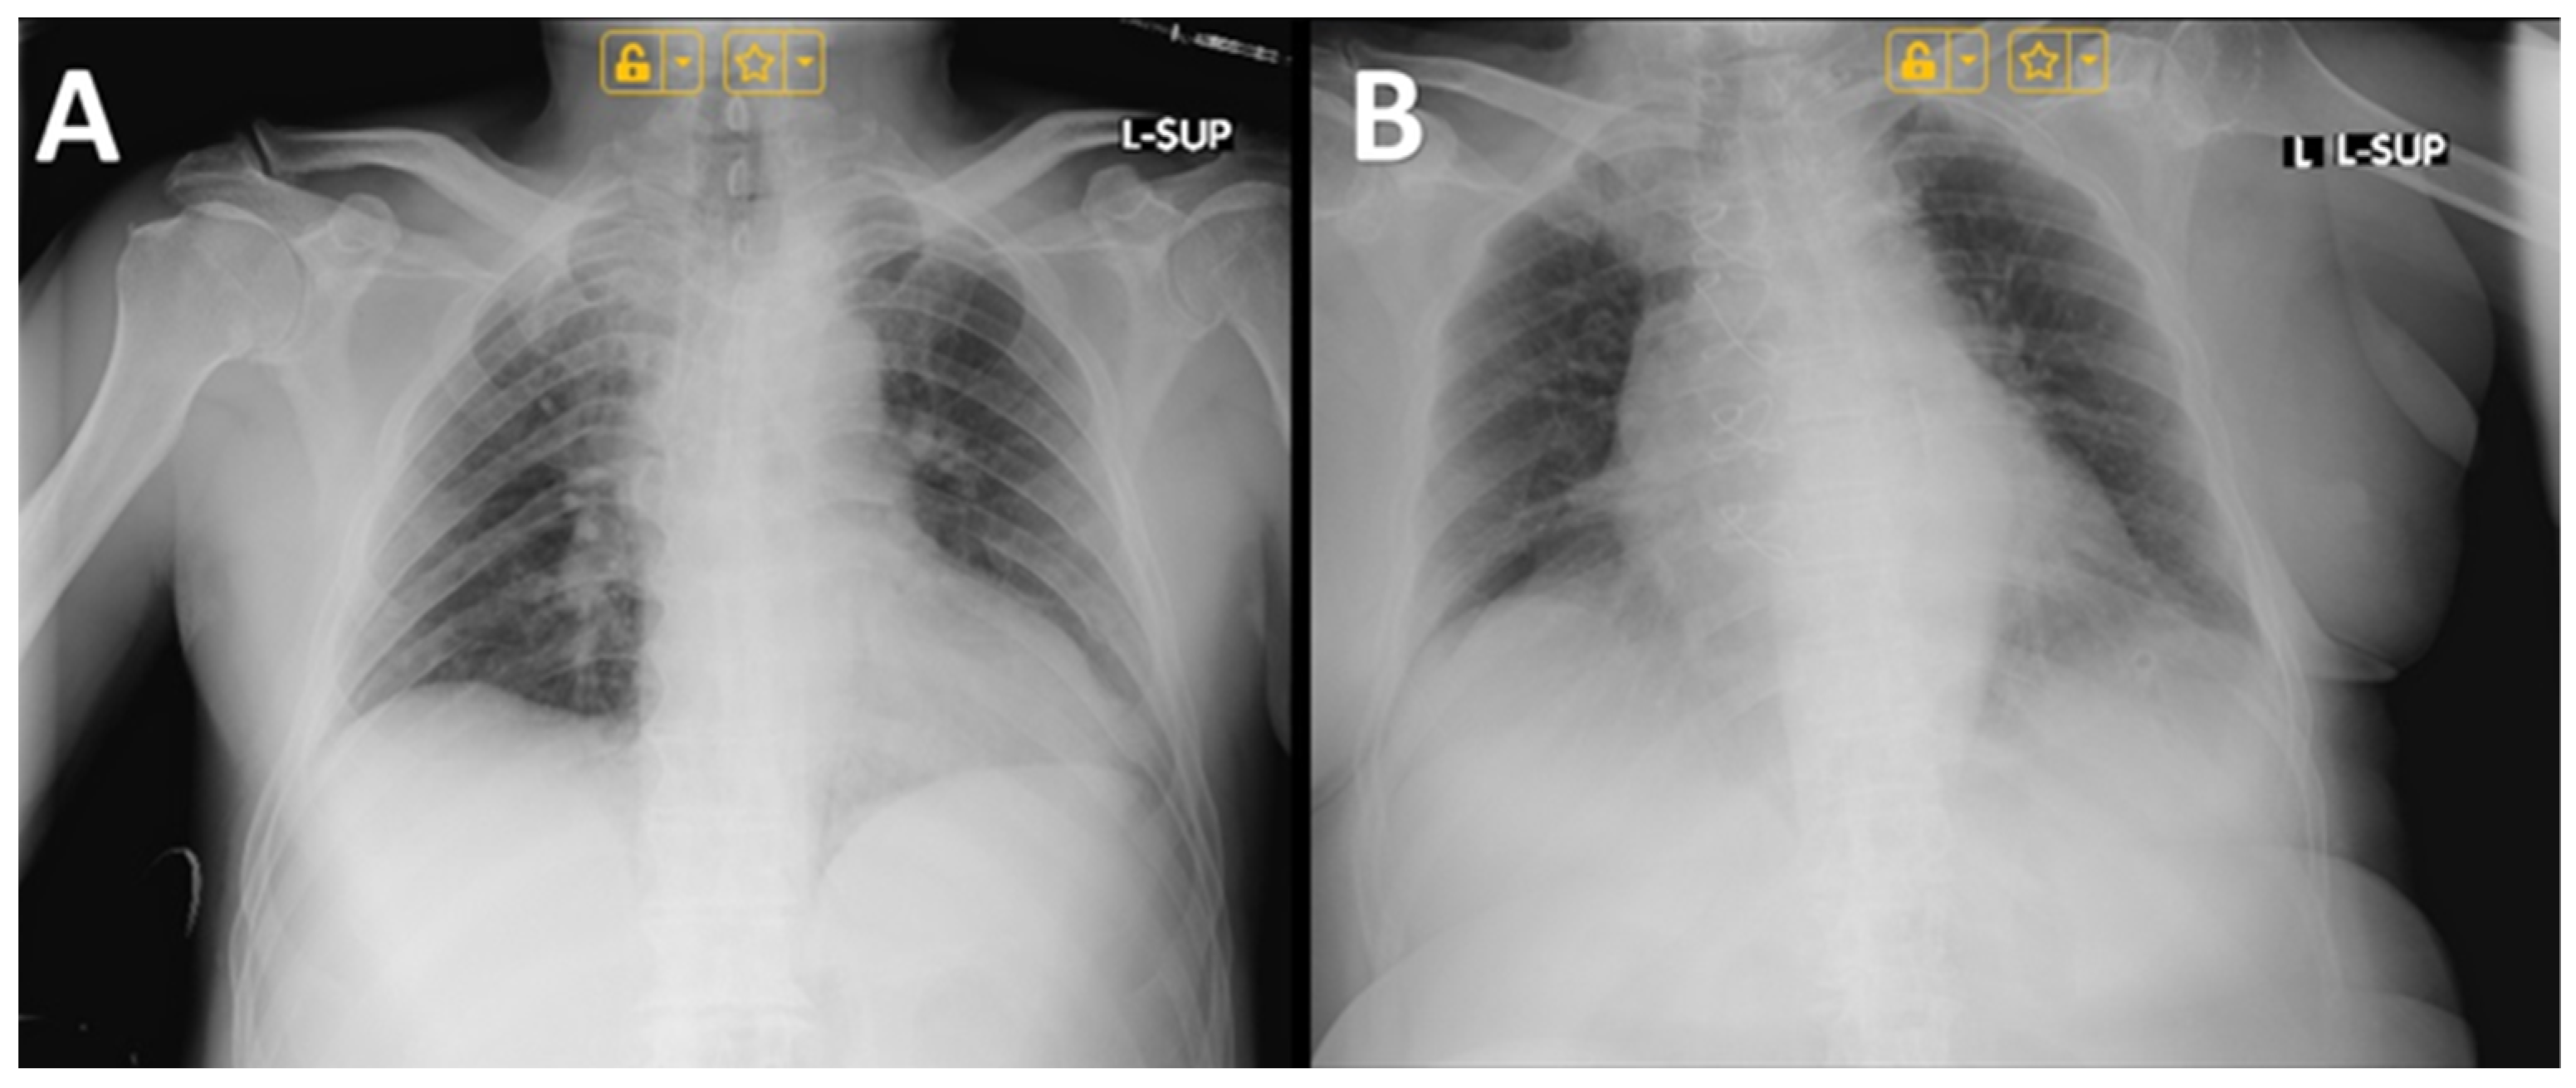

4.3. Imaging Findings